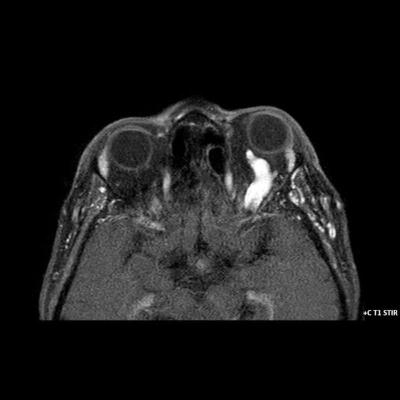

- B) Pre ve post-kontrast yağ basklılı T1A görüntüler incelendiğinde superior oftalmik venin (oklar) kontrast madde verildikten sonra homojen dolum gösterdiği, dilate ve tortiyoze görünümde olduğu izleniyor.

- BT ve MRG: Propitozis, ekstraokuler kaslarda genişleme, superior oftalmik vende genişleme ve tortiyozite, ipsilateral kavernöz sinüste genişleme gösterilebilir. Serebral venöz konjesyonu olan ve intrakraniyal basınçları yükselen hastalarda serebral ödem, hemoraji, leptomeningeal ve kortikal venlerin dilastasyonunu görülebilir. Bunlara ek olarak travmaya sekonder olgularda BT ile eşlik eden fraktürler gösterilebilir.